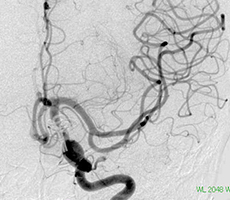

[手術方法]

左前頭側頭開頭で動脈瘤クリッピング術を行った。手術中は脳血管撮影装置を用いたHybrid手術を施行し、動脈瘤の消失を手術中に確認する。

手術中の脳血管撮影画像

-

(手術前) -

クリップ留置後、瘤(こぶ)は消失 -

(手術後) -

患者様は術前からあった左視力低下以外に神経症状なし。元気に自宅退院されました。